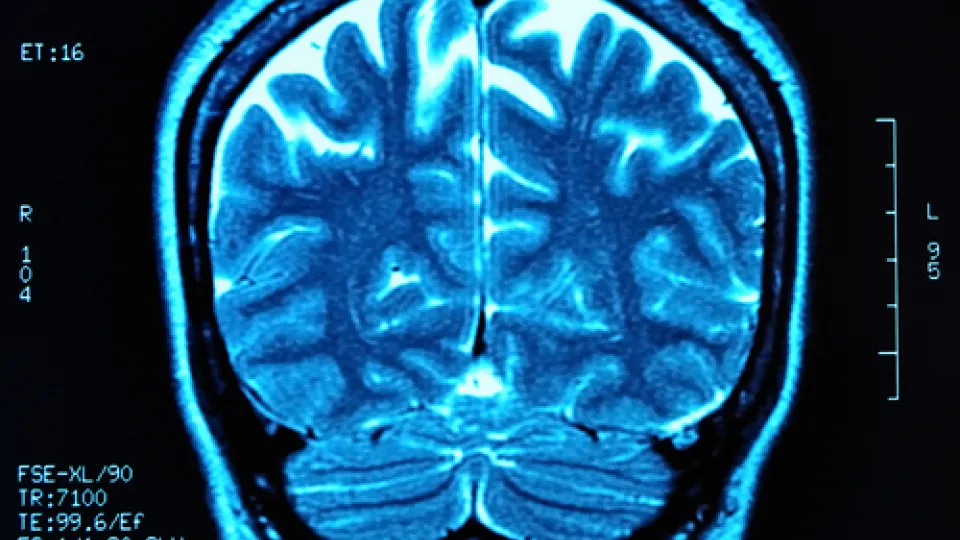

Take becoming a Neurodiagnostic Technologist (NDT). In short, technologists employ specialized equipment to determine how effectively a patient's nervous system is functioning.

The test results they gather enable physicians to diagnose and treat conditions such as degenerative brain diseases, headaches, dizziness, seizure disorders, strokes, mental disorders, and sleep disorders.